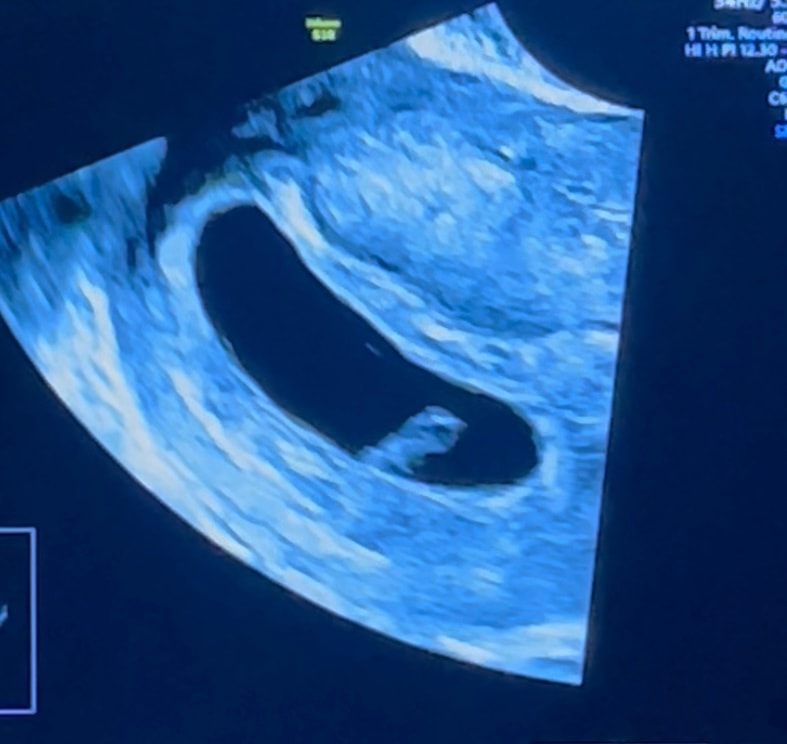

6 недель и 4 дня

У нас получилось! Я беременна!

Моя крошка ❤️🙏🏻 Расти здоровеньким ❤️Я тебя так уже люблю 💖

Мы с папой и двумя братиками тебя очень ждем 🥺